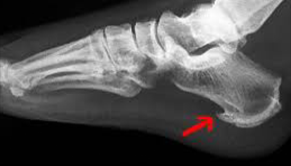

Patní ostruha a plantární fascitida

Patní ostruha

Ostruha patní kosti trápí lidi používající nesprávnou obuv, dále ty, kteří patu trvale přetěžují chybným stereotypem chůze nebo běhu. Ostruha patní kosti může být pozůstatek poranění paty a taktéž součástí skupiny revmatických chorob.

K nejčastějším příznakům ostruhy patní kosti patří bodavá bolestivost v patní krajině, která se objevuje při nášlapu a mnohdy i při pouhém doteku paty a je lokalizována vprostřed paty, může vystřelovat do plosky. Dále se může objevit zarudnutí paty, otok a později i různé nárůstky v oblasti úponu Achillovy šlachy - "Haglundova pata"